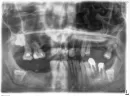

Скорее всего, придётся удалить зубы 17, 16, т.к. они выдвинулись вниз из-за отсутствия нижних зубов. Также необходимо удалить зуб 28 по той же причине.

Если рассматривать дентальную имплантацию, то на верхней челюсти необходима костная пластика (синус-лифтинг) с двух сторон из-за недостаточного объёма костной ткани.